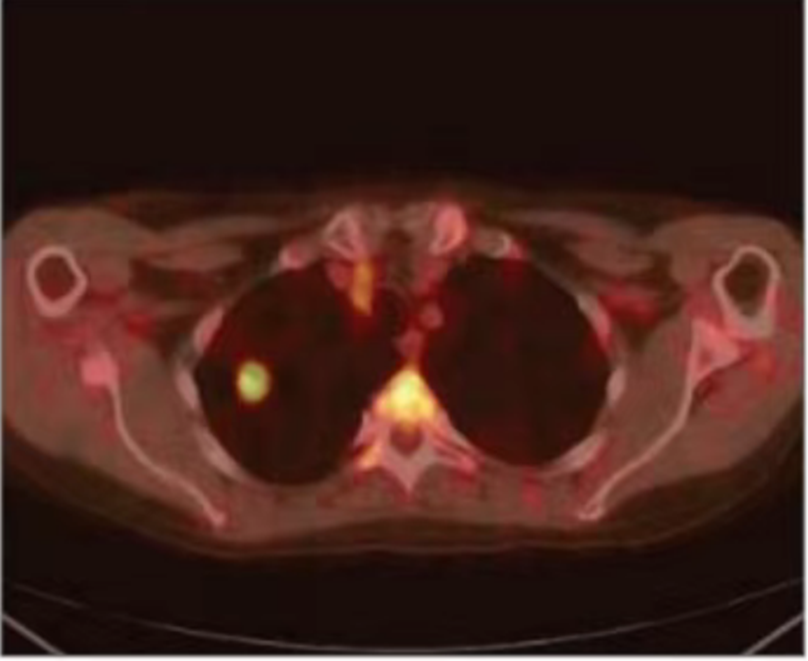

Results and Follow-up

At 11 months post-treatment, PET-CT imaging showed no evidence of active disease, with only residual scarring visible. PET results were negative for metabolic activity. The patient remained in good overall condition, with no reported adverse complications following CyberKnife treatment.